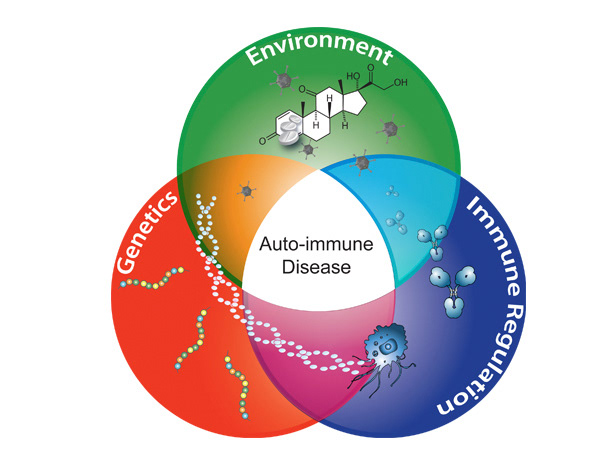

BioArt

Illustrating molecular method of action & drug delivery systems